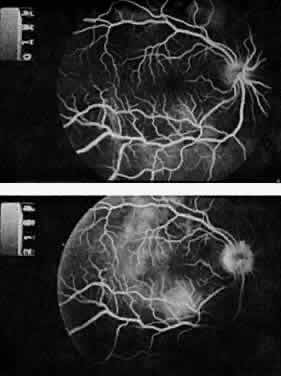

The ocular manifestations of antiphospholipid antibodies include retinal venous and arterial occlusions, amaurosis fugax, diplopia, and visual field loss.34,35 Extensive vasoocclusion, neovascularization, and vitreous hemorrhage may occur (Fig. 3). Treatment consists of photocoagulation for the neovascularization and systemic anticoagulation and immunosuppression. Vitrectomy may be required for vitreous hemorrhage. The role of systemic treatment of lupus anticoagulant in the management of ocular disease is unclear. Some investigators suggest that systemic anticoagulation be started promptly.36 The optimal duration of anticoagulation and whether antiplatelet therapy should be used are not known however. The optimal use of corticosteroids or other immunosuppressive drugs such as cyclophosphamide and azathioprine also is unknown. Two reports have found an association with the antiphospholipid syndrome and some additional retinal conditions. One report also has associated the primary antiphospholipid syndrome with central serous chorioretinopathy.37 In addition, lupus anticoagulant positivity could represent an additional risk factor for diabetic retinopathy according to a recent report.38